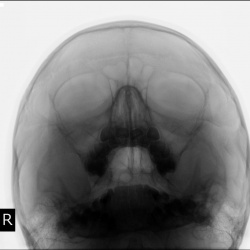

Направлен на рентгенографию ППН. Ваше мнение уважаемые коллеги?

Пациент направлен на рентгенографию придаточных полостей носа.

Пациент направлен оториноларингологом на рентгенографию придаточных полостей носа.Ваше мнение коллеги?  Врач оториноларинголог вынес вердикт - "НОРМА".